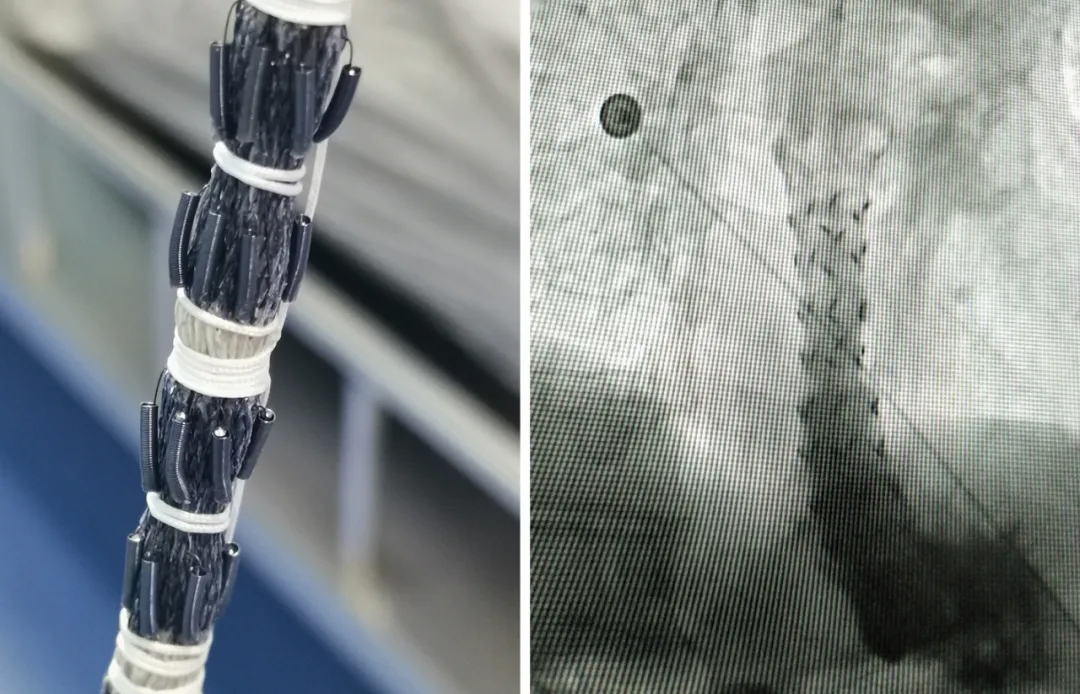

粒子支架技术治疗食道癌,采用的是可以360度旋转的记忆合成柔软金属支架,支架上安装的是125-碘粒子,其半衰期为59.6天,粒子平均能量30KeV,粒子在肿瘤内部持续放射出低能量γ射线,近距离照射肿瘤组织,分别在1.7cm范围内最大限度杀灭肿瘤细胞,能迅速杀死肿瘤细胞,截断肿瘤细胞扩散的途径,对正常组织无伤害,从而达到治疗目的。采用粒子支架技术治疗食道癌,对正常组织没有任何伤害,同时撑开食管腔,使食物顺利通过。安全、无创伤,无痛苦,不伤害机体组织,治疗后即可正常吃饭,总体费用低,特别是对年龄偏大、治疗无望、放化疗无效的患者,更是一种新的选择。

为了解决患者不能进食的痛苦,提高肿瘤病人的生存质量,2020年11月26日,运城同德医院核医学科主任原武红、副主任陈艳峰专家团队在郑州大学第一附属医院朱明教授的指导下,在数字减影血管造影机(DSA)引导下成功完成了食管癌食道梗阻患者食管粒子支架植入术。 术中顺利,术后患者无不适。患者术后4小时开始饮水,术后12小时开始进食流质食物,目前患者进食半流食无明显咽下困难。